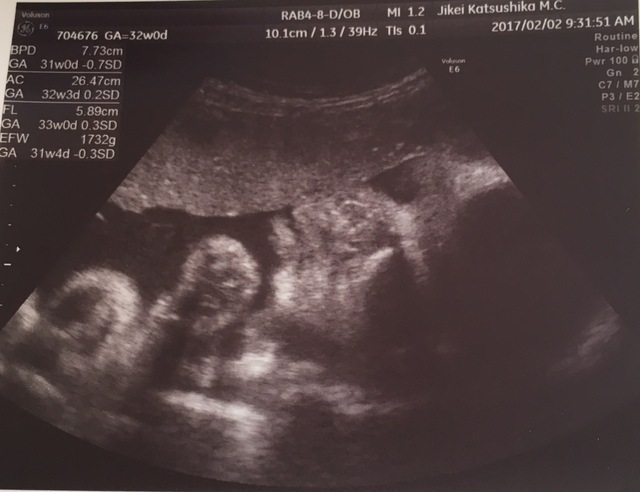

32週0日(32w0d・女の子)|えみちん99 さん(25歳)

エコー写真撮影時のエピソード:

週数よりもいつも小さめだと言われており、心配でしたが、元気だと言われて安心していました。エコーの時は寝てることが多かったけど、いつもお顔は見せてくれていたので、うれしかったです。月に1回のエコーで成長を見るのが楽しみでした。